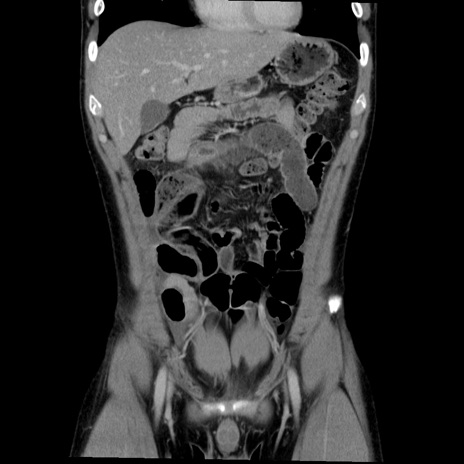

症例36(冠状断像)

【症例】20歳代 男性

【主訴】心窩部痛

【現病歴】今朝より上腹部痛あり。一旦軽快していたが再度出現したため救急要請。昨日夕に白身の魚を含む刺身を食べた。

【身体所見】BP 136/89mmHg、HR 74/min、BT 37.0℃、腹部:膨満、軟、心窩部に圧痛あり。反跳痛なし、筋性防御なし、腸雑音やや亢進あり。

【データ】WBC 17700、CRP 0.48